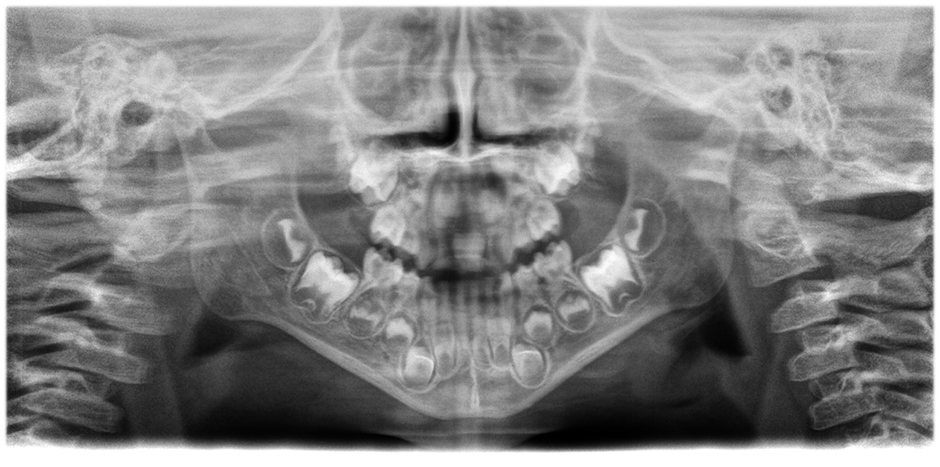

• Panorama images of outstanding clarity and definition

with the innovative 21-layer autofocus system seamlessly integrated with a patient positioning correction.

Move the slider to see the difference (left image without, right image with autofocus and patient positioning correction)